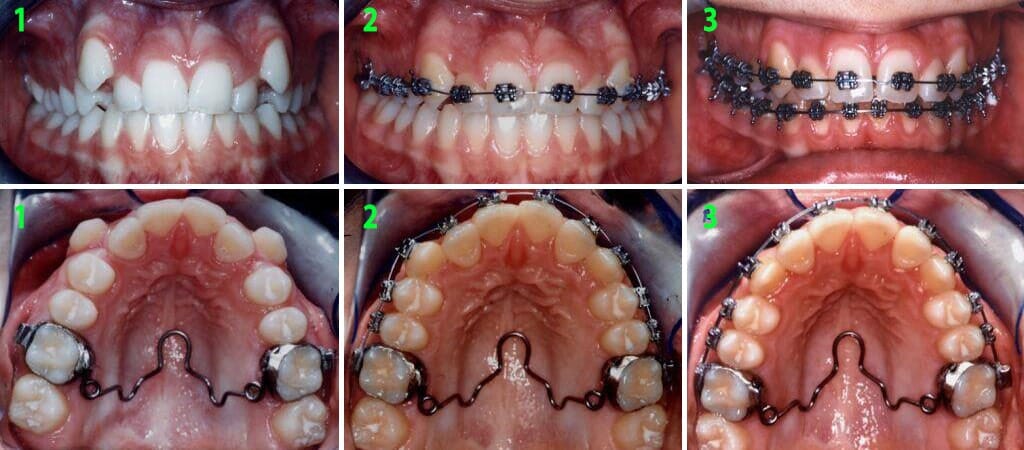

תמונות בתוך הפה

אחרי

תמונות מתוך הפה, אחרי

לפני

תמונות מתוך הפה, לפני

במקרים שבהם הלסת העליונה אחורית ללסת התחתונה ניתן למשוך את הלסת העליונה קדימה בצורה אופטימלית תוך הפיכת הניבים הנשירים לשתלים אורתודונטיים נספגים מעצמם. ד"ר גלעד הר- ציון הוא אחד מהאורתודונטים הבודדים בישראל אשר משתמשים ומיומנים בשיטה זו, אשר מביאה לתוצאות טובות גם במקרים קשים במיוחד.